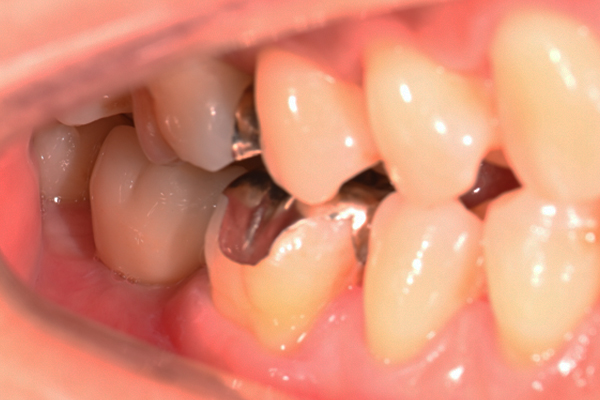

| 主訴 | 奥歯で噛めない、顎が痛い |

|---|---|

| 治療内容 | 奥歯のインプラント治療、前歯・奥歯の被せ物治療 |

| 治療期間 | 6ヶ月 |

| 治療費 | 350万円 |

| 治療リスク | 被せ物をつけた初期の段階で歯がしみることがある(時間とともに改善する) インプラント治療後に3日程度痛みと腫れを伴うことがある |